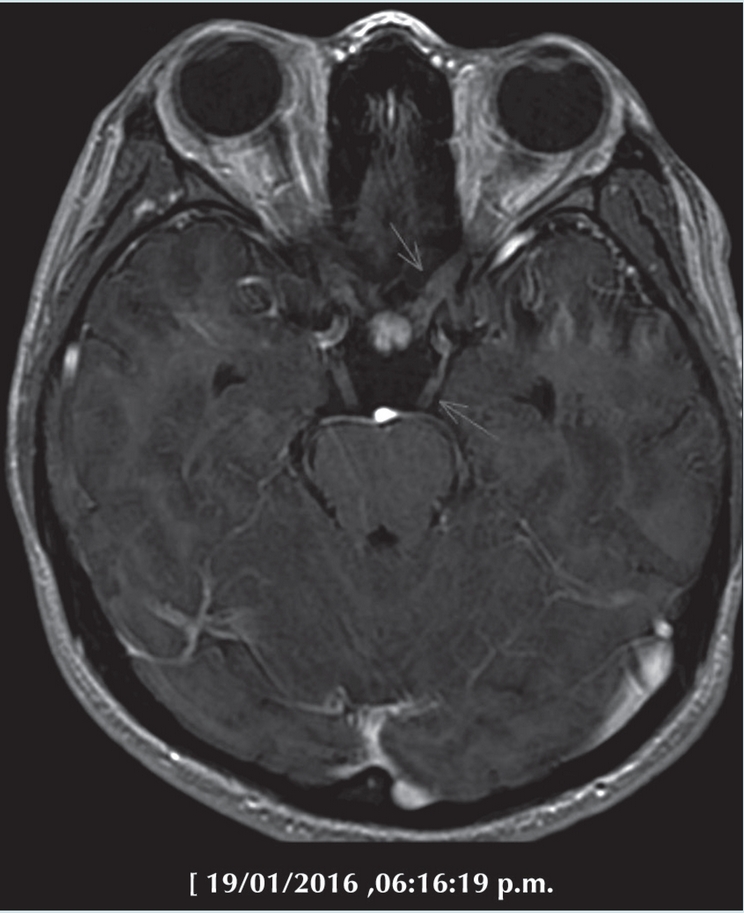

Los síntomas neurológicos obligaron a complementar con estudio de resonancia magnética de encéfalo y neuroeje contrastada con gadolinio, donde se demostró infiltración al sistema nervioso central de tipo leptomeníngeo, caracterizada por engrosamiento y reforzamiento de pares craneales y de la cauda equina (Figuras 3 y 4) que diversos autores documentan entre un 2 y 27% según la agresividad en el linfoma no Hodgkin y solo menos del 0.5% en linfoma de Hodgkin.2

Al momento de su ingreso, fue vista por Neurología y al considerar que se trataba de un cuadro agudo que sugería un proceso inflamatorio y objeto de manejo inmediato se transfirió al Servicio de Infectología con el diagnóstico de presunción de meningitis. Los estudios de imagen, como ya desglosó el Dr. de Uña, muy pronto esclarecieron la naturaleza del problema. La resonancia magnética reveló alteraciones en pares craneales y en médula espinal y la placa de tórax documentó la hipertrofia mamaria y mostró una gran masa en mediastino anterior y medio.